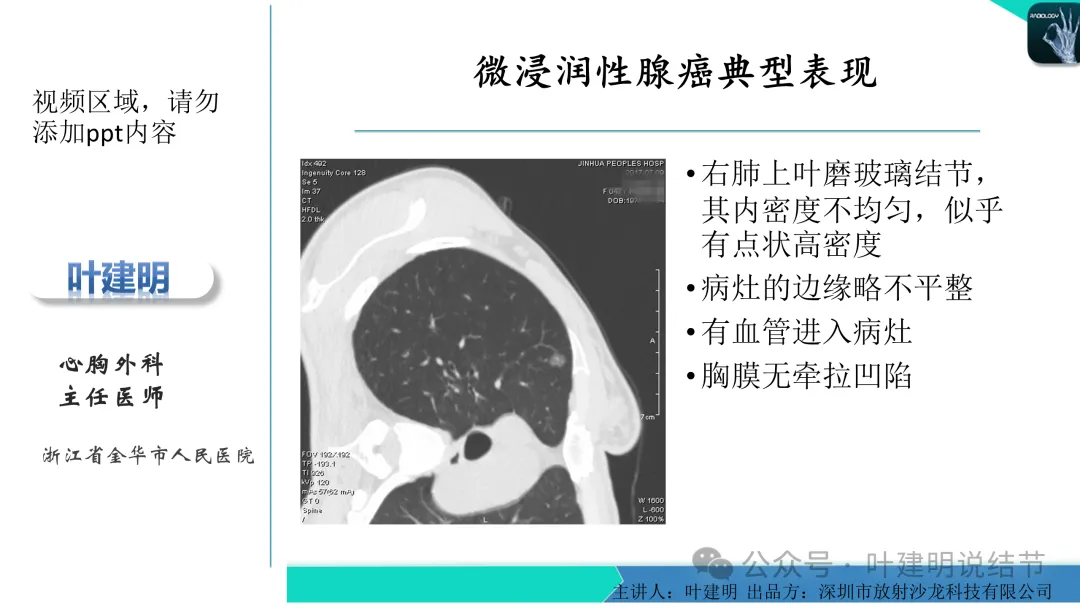

早在2020年时,我受邀在《放射沙龙》做过一个系列的精品课,当时专门总结分析过各类良恶性肺结节与肿块的影像特征,这是当时关于微浸润性腺癌影像特征的分析,今天看来仍基本不太需要改变,大家有兴趣的可以参考: